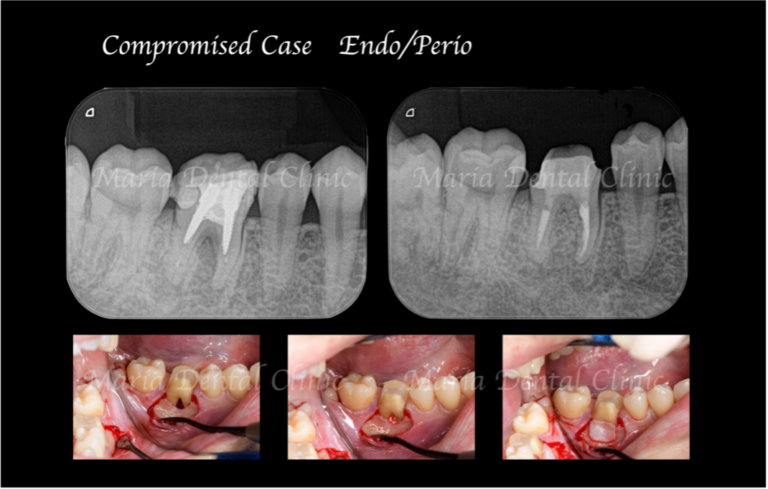

【症例】難症例・根の病気と歯周病が併発した症例2(世界基準の精密根管治療と最先端の歯周組織再生療法を用いて全ての問題を解決)